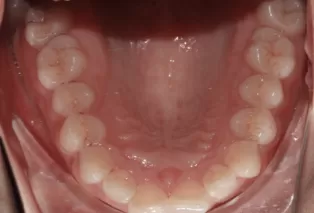

Photos intra-orales après traitement